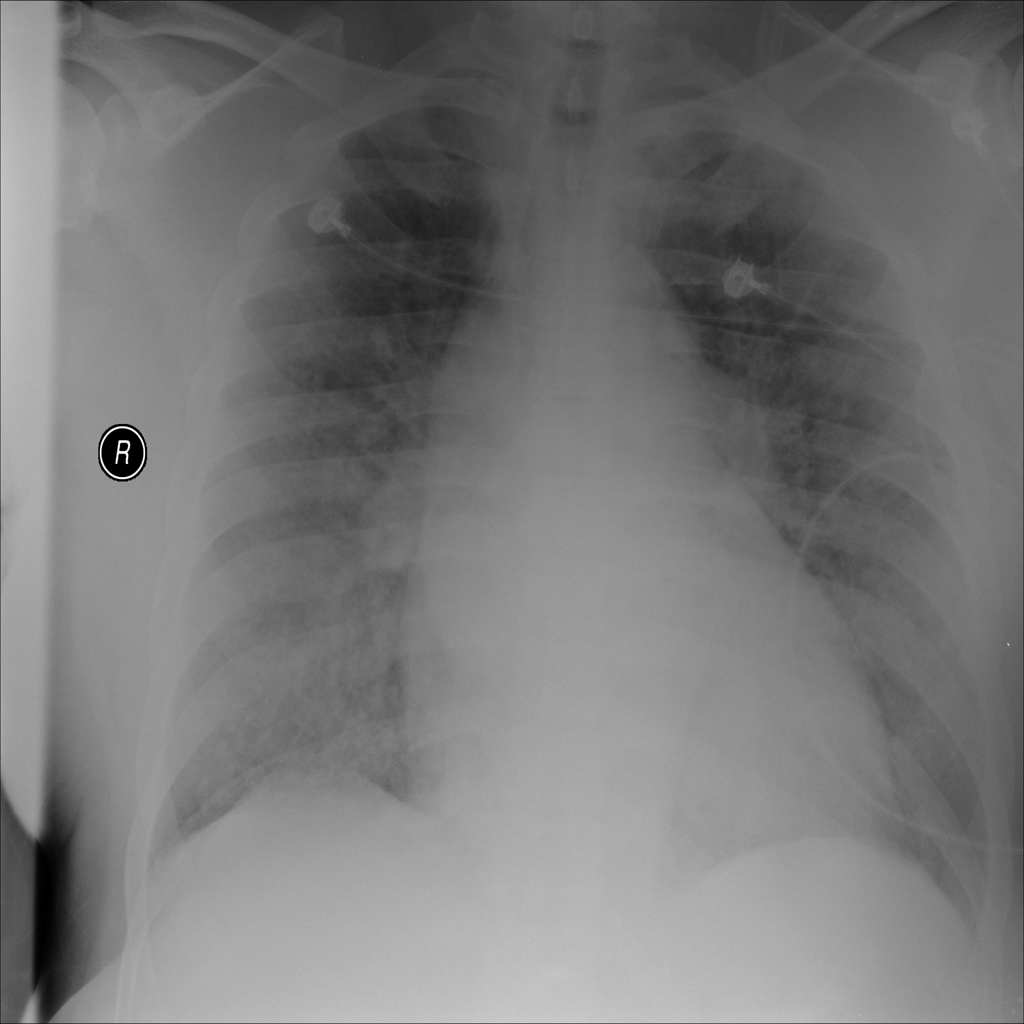

PAT-E828 · IMG-005Edema

PAT-E828 · IMG-005

AP